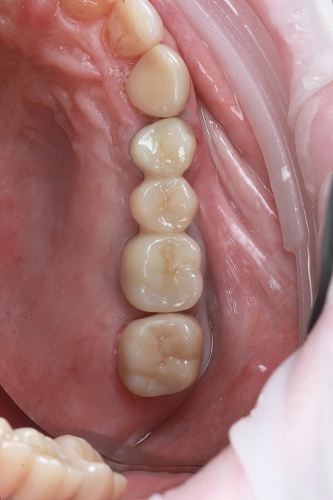

На фото — работа нашего врача-хирурга-имплантолога Федотова Руслана Валерьевича. В этом случае была успешно проведена имплантация с синус-лифтингом — процедурой, которая позволяет поднять дно гайморовой пазухи и создать необходимое пространство для установки импланта.